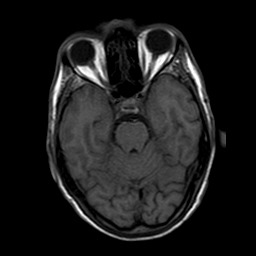

A 50 years old man with...